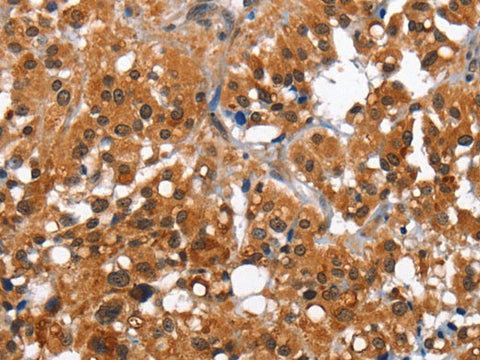

Reactivity Human, Mouse

Applications IHC

Immunogen Recombinant protein of human CAMK1D

Cellular Localization Cytoplasm. Nucleus. Predominantly cytoplasmic (Probable). Also nuclear upon activation.

Research Areas Cancer,  Cell Biology,  Signal Transduction

IHC 1:50-1:200